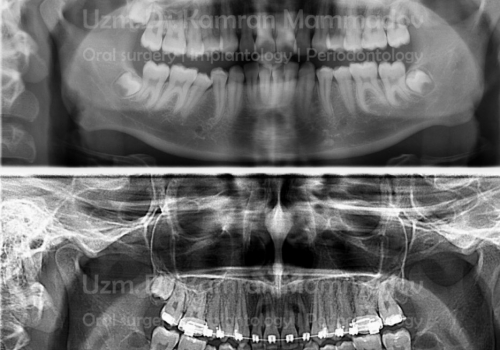

Normal halda insanın diş sırasında hər çənədə iki ədəd olmaqla, ümumilikdə dörd agıl dişi mövcuddur. Ağıl dişinin çıxması bəzi şəxslərdə heç bir kliniki əlamət və ya şikayətə səbəb olmasa da, bir çox hallarda müəyyən kliniki əlamətlərlə öyünü biruzə verir. Bu əlamətlər əsasən çənənin arxa tərəfində təzyiq, çənəni açıb baglama əsnasında agrı və məhdudlaşma kimi özünü göstərə bilir. Bu hallarda mütəxəssis konsultasiyasının önəmi olduqca böyükdür. Belə ki müayinə zamanı cərrah-stomatoloq kliniki və radioloji dəyərləndirmə apararaq dişin dogru pozisiyada yerləşib yerləşmədiyi, dişləmə çıxma ehtimalını, agıl dişinin çənəyə görə ölçüsü və çənə darlıgı kimi durumları dəyərləndirərək tətbiq edilməli olan müalicə taktikasını müəyyən edir.

- Retensiyon ağıl dişinin spontan və ya ortodontik olaraq dişləmə çıxma ehtimalı mövcud deyilsə

- və eyni zamanda digər bir dişin əvəzləyicisi kimi istifadə olunmayacaqsa (transplantasiya və ya ortodontik)